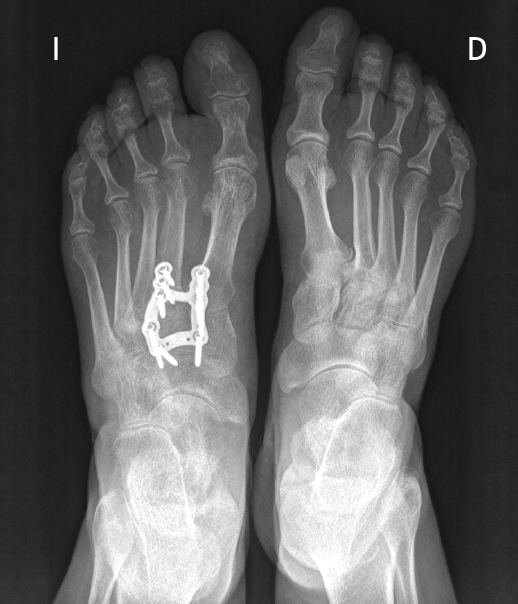

Figura 2. Tratamiento quirúrgico mediante artrodesis con placa en proyección dorsoplantar.

Existen distintas opciones de osteosíntesis con tornillos y/o placas. Actualmente, disponemos de diferentes diseños de placas: placas de tipo “Pi” que fijan CMM1-CMM2, placas plantares, mediales, medioplantares o dorsales. Recomendamos el empleo de placas “Pi” si es preciso artrodesar CM-M2 y el uso de placas medioplantares o plantares para la artrodesis aislada de CM-M1, que desde el punto de vista biomecánico son más apropiadas (Figuras 1 a 3). Otro tema de debate es el empleo de injerto óseo esponjoso autólogo o de sustitutivos óseos como la matriz ósea desmineralizada o trifosfatos cálcicos. Recomendamos, especialmente en pacientes menores de 50 años, el empleo de injerto autólogo de cresta ilíaca.